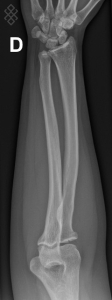

Radiographie de l’Avant-bras (radius, cubitus)